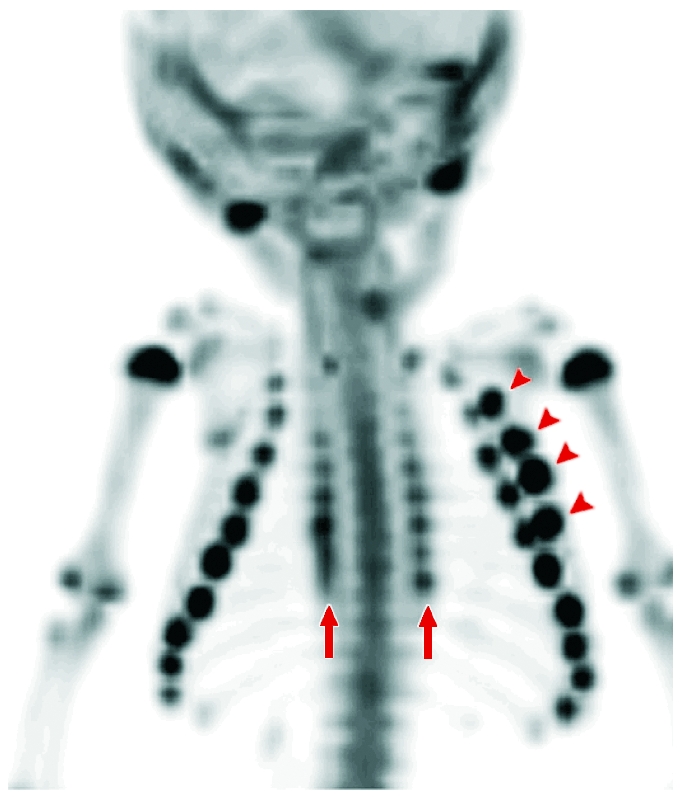

Durch die Verabreichung von IASOflu(R) können Knochenmetastasen

bei Erwachsenen leichter lokalisiert und lebensrettende Maßnahmen

rascher eingeleitet werden. Weiters dient es zur Diagnose von

Rückenschmerzen mit zweifelhafter Herkunft. Diese Möglichkeit ist bei

konventionellen bildgebenden Verfahren nicht gegeben. Ein besonderes

Augenmerk gilt dem Einsatz von IASOflu(R) bei der Diagnostik von

Knochenläsionen mit Verdacht auf Misshandlungen bei Kindern. Gerade

in diesem sensiblen medizinischen Bereich wird der Bedarf solcher

Diagnoseverfahren steigen.